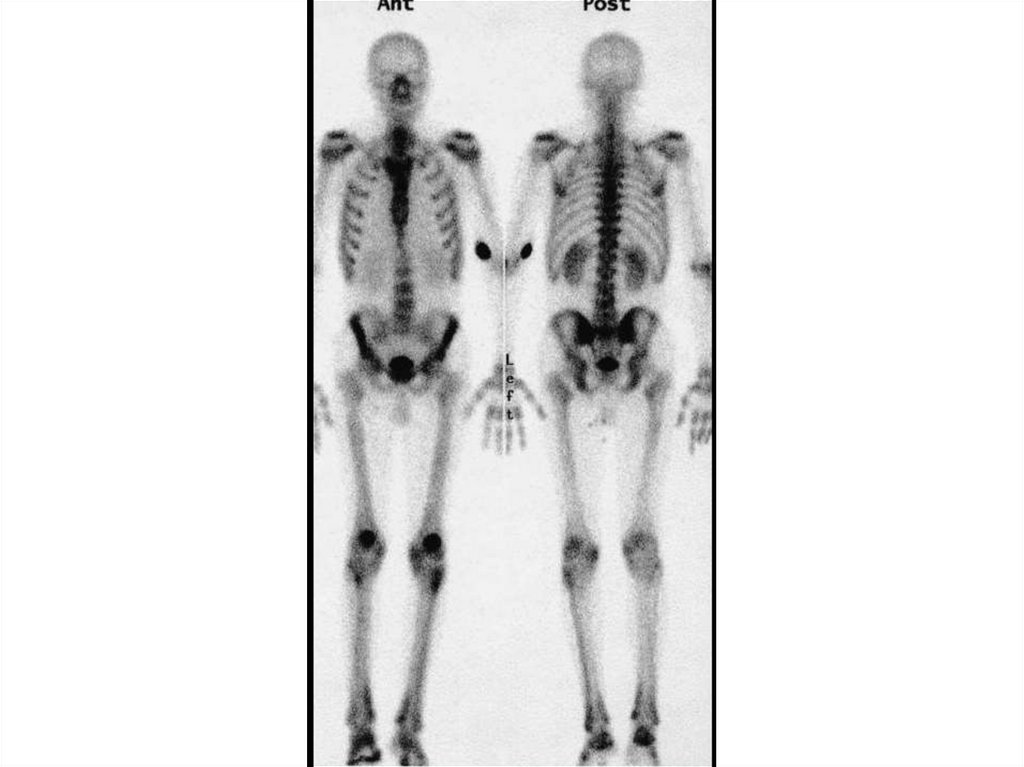

Local and intrathoracic manifestations

38.

39.

A 45-year-old woman with a 27-pack-year history of smoking presented for evaluation of

progressive distal finger enlargement and polyarthralgias, which had developed over a period of

18 months

Faller B and Atkinson J. N Engl J Med 2008;359:e15